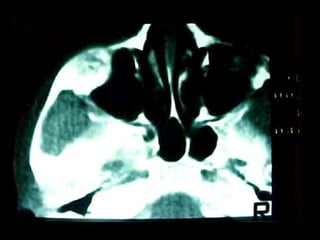

Osteomielitis

La osteomielitis es una infección súbita o de larga data del hueso o médula

ósea, normalmente causada por una bacteria piógena o micobacteria y

hongos. Los factores de riesgo son trauma reciente, diabetes, hemodiálisis y

drogadicción intravenosa.

La Osteomielitis se define como una inflamación extensa del hueso,

implicando a toda porción esponjosa, medular, cortical, periostio, vasos

sanguíneos, nervios y epífisis. La inflamación puede ser aguda, subaguda o

crónica y presenta un desarrollo clínico diferente según su naturaleza (1-5).

En el caso de los maxilares se considera la infección odontógena como la

causa más frecuente de osteomielitis. Se puede presentar a cualquier edad

con un predominio entre los hombres. Afecta principalmente al maxilar

inferior. En el maxilar superior es más raro, debido a una mayor

vascularización .